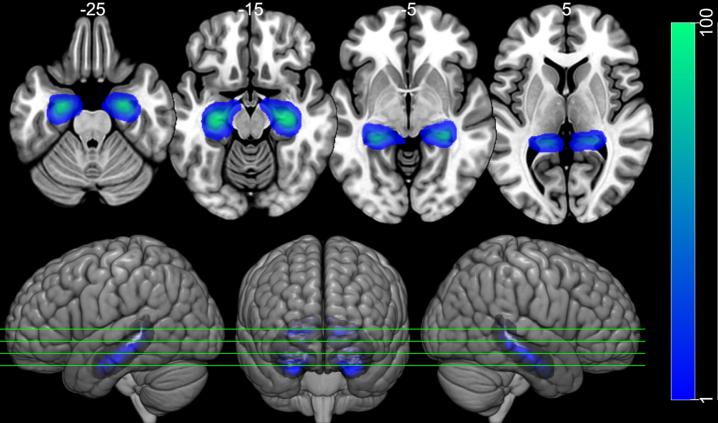

Forty-six older adults were included, among them Aβ PET PIB positive (PIB+) aMCI (N = 17), Aβ PET PIB negative (PIB-) aMCI (N = 15), and HC (N = 14). Hippocampal volume and function were analyzed using Freesurfer v6.0 and FSL for news headlines episodic memory fMRI task, and logistic regression for group classification in conjunction with episodic memory task and traditional neuropsychological tests.

The aMCI PIB+ and PIB-patients showed significantly worse performance in relation to HC in most traditional neuropsychological tests and within group difference only on story recall and the ecological episodic memory fMRI task delayed recall. The classification model reached a significant accuracy (78%) and the classification pattern characterizing the PIB+ included decreased left hippocampal function and volume, increased right hippocampal function and volume, and worse episodic memory performance differing from PIB-which showed increased left hippocampus volume.